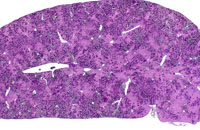

Low magnification of erythroleukemic infiltrates in the liver.

Examples of erythroleukemia in a Tg.AC mouse.